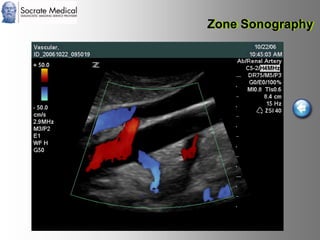

Il documento presenta la tecnologia della zone sonography, che promette una rivoluzione nel campo degli ultrasuoni, superando i limiti dei sistemi tradizionali grazie a metodi di acquisizione dati più veloci e una gestione delle informazioni migliorata. Questa tecnologia consente una maggiore definizione dell'immagine, una riduzione degli artefatti e un'ottimizzazione del processo diagnostico, con vantaggi in termini di tempo e costi. Inoltre, il channel domain processing e la zone speed technology offrono applicazioni avanzate e miglioramenti nella sicurezza diagnostica.